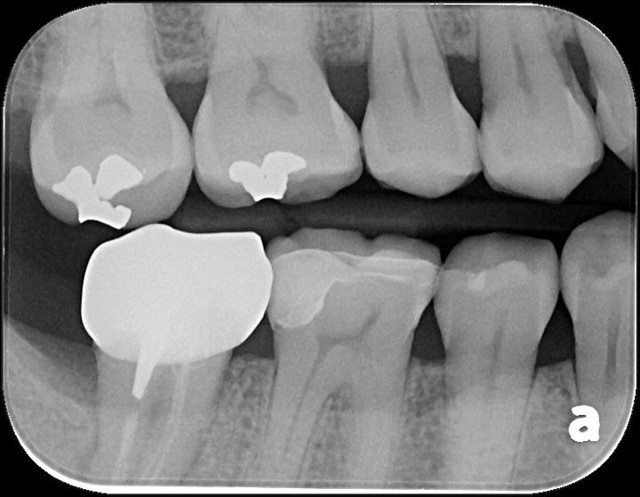

治療前,嚴重蛀牙,咬頭受損

蛀牙未到牙髓

當蛀牙破壞程度大